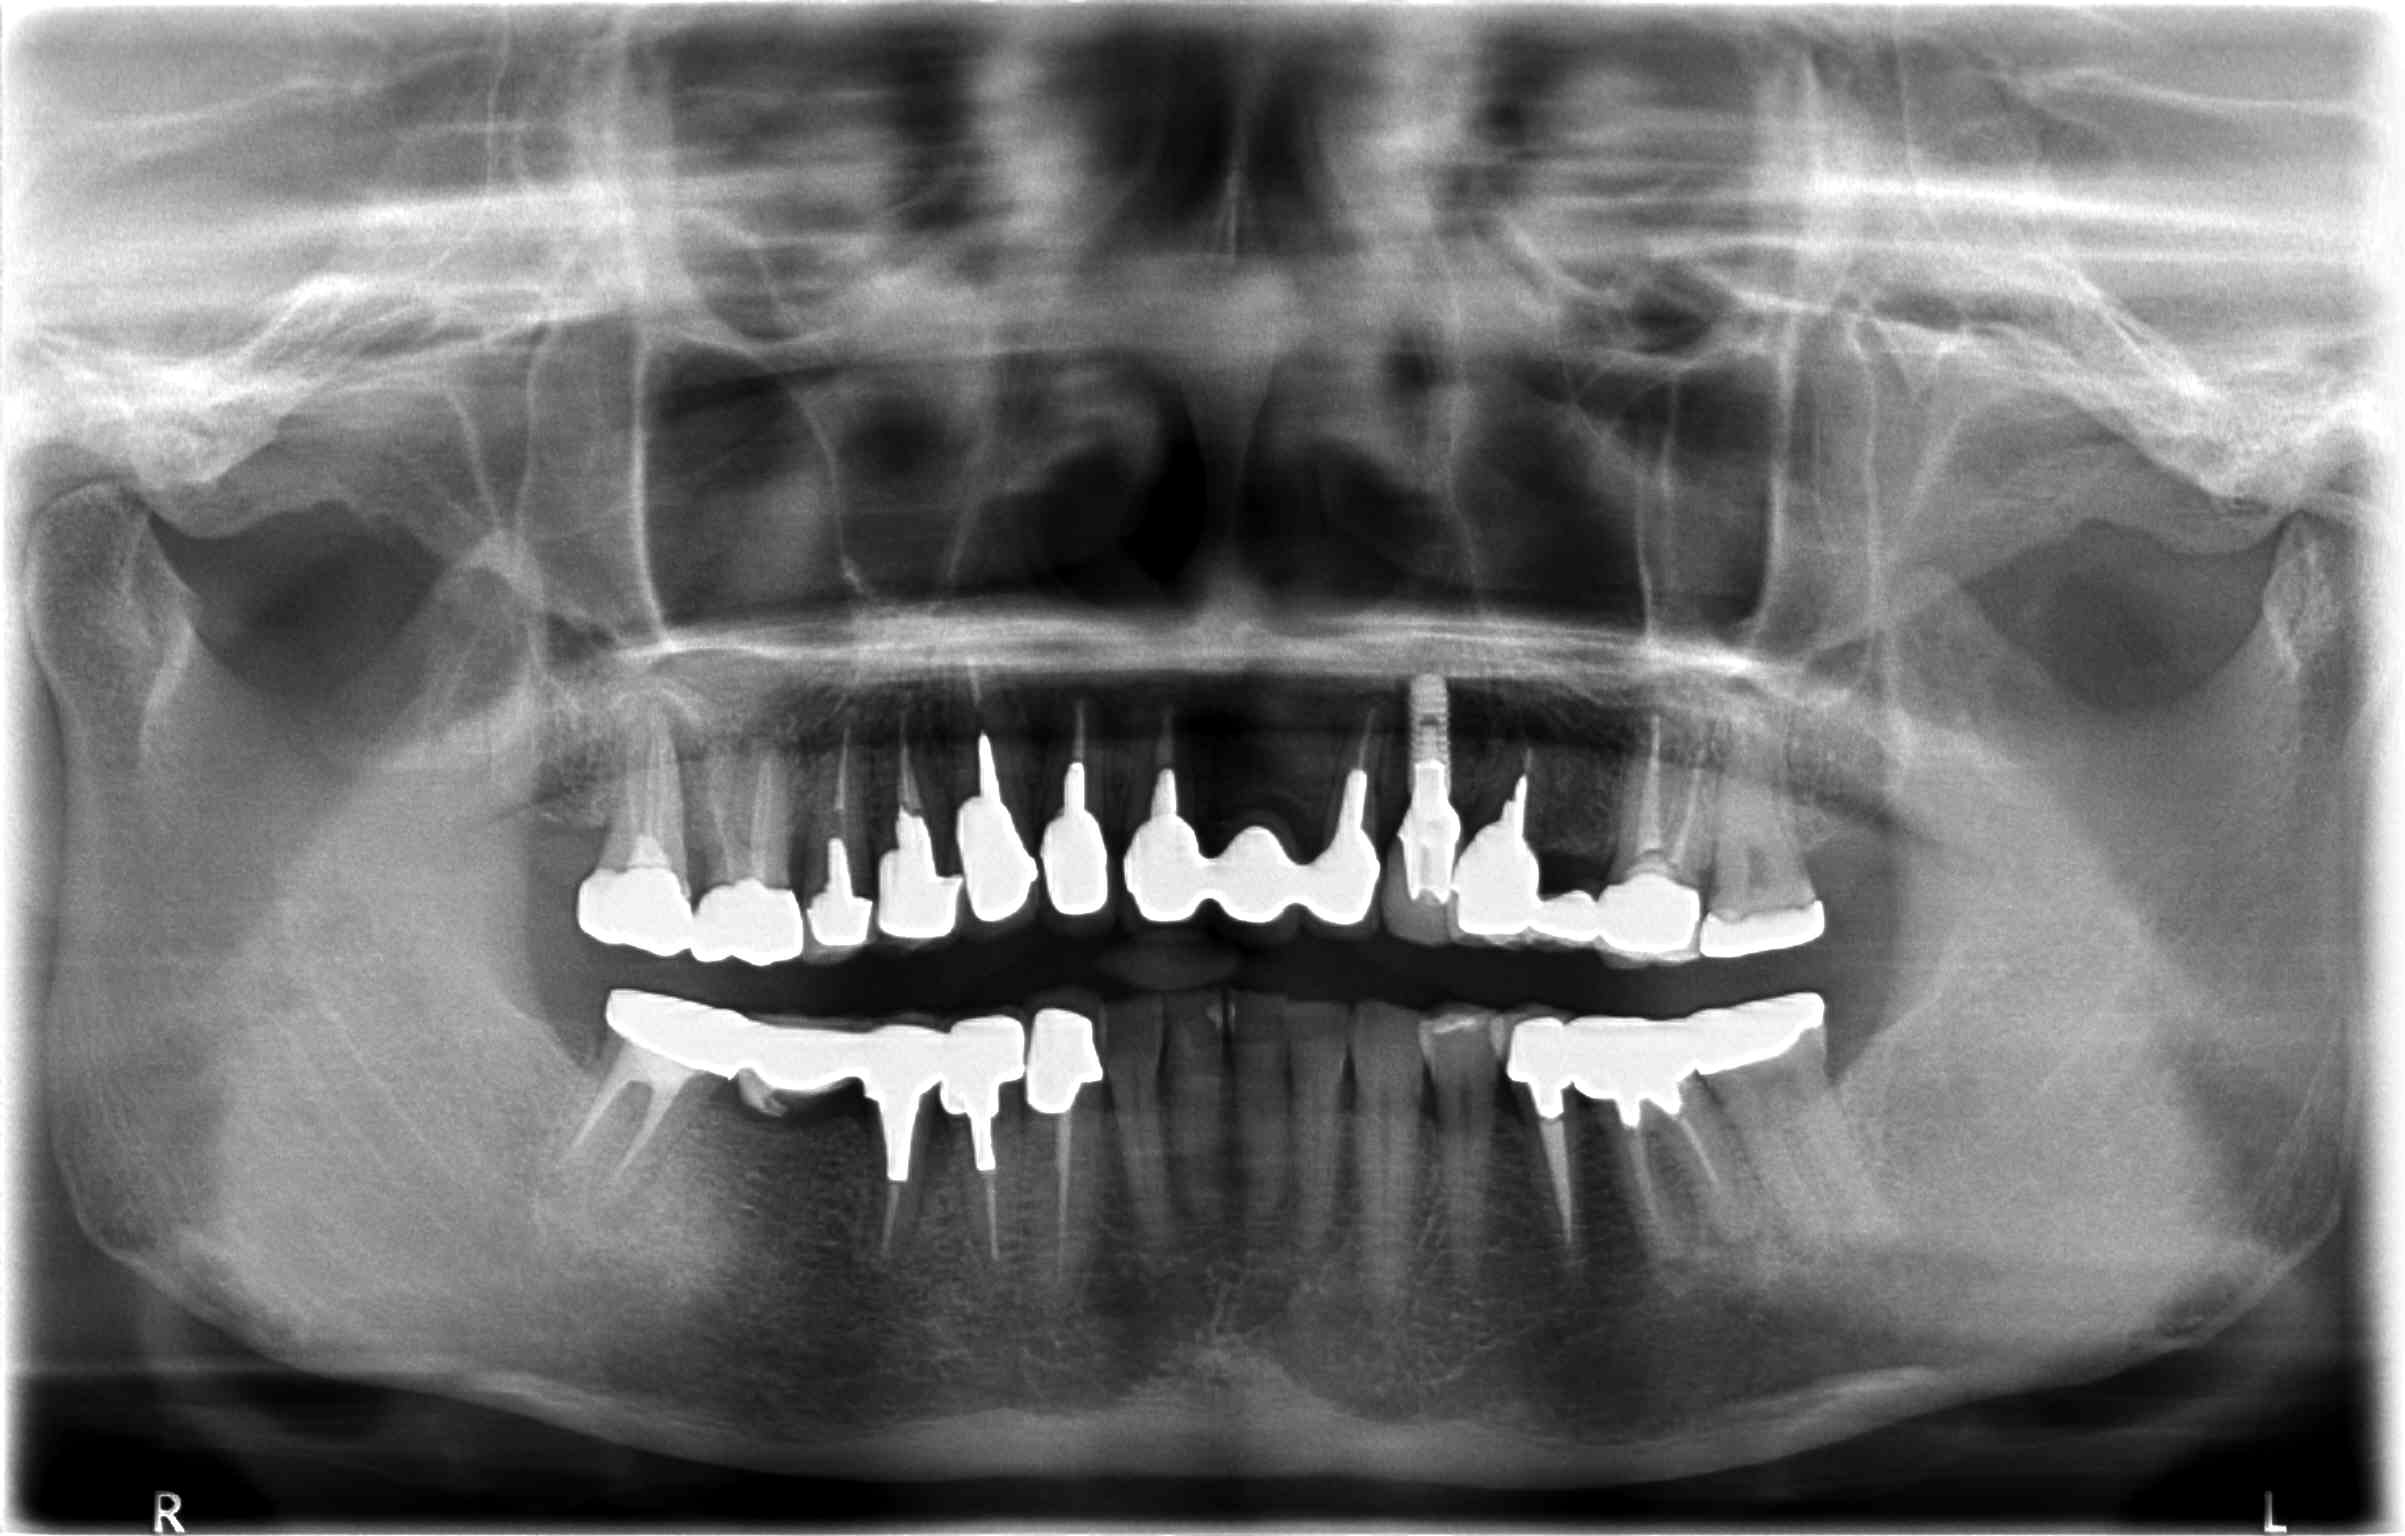

症例④

複数の歯に及び歯が失われているためCT画像上で診断と設計を行い、理想的な位置に歯を作ることができるように、サージカルガイドと言われるインプラント手術補助用マウスピースを用いてインプラント手術を行った。

術前レントゲン写真

-

術後レントゲン写真